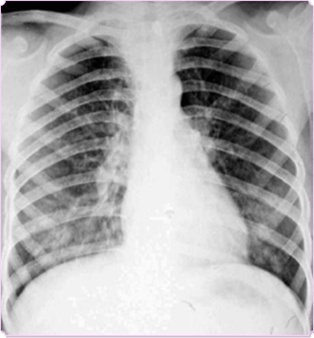

图中可见右上叶“斑点花”,根据公式诊断为小叶性肺炎